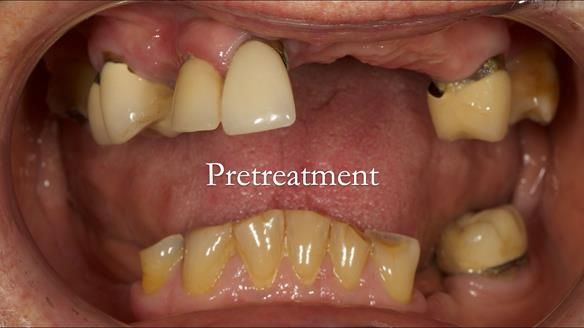

Aesthetically and functionally poor RPDs were replaced for Eileen, a 74 year old woman.

Referred to me by her general dental practitioner specifically for replacement RPDs.

Dental concerns

“Top denture loose making conversation difficult at times. Also, appearance isn’t good. Teeth uneven”

Diagnoses

- Missing teeth in the upper and lower jaws

- Upper and lower metal based RPDs, poorly fitting, worn occlusal surface, reverse curve aesthetics, lacking support

- Poor dental appearance with reverse incisal curve

- The upper right central and lateral incisors with post crowns. Healthy and functionally secure but with poor appearance, contributing to the reverse curve.

- Moderate to heavily restored dentition with deep overbite (Class 2 div II)

- Yellowish lower front teeth with small amount of wear.

- The lower right canine (LR3) is worn with MOD cavity.